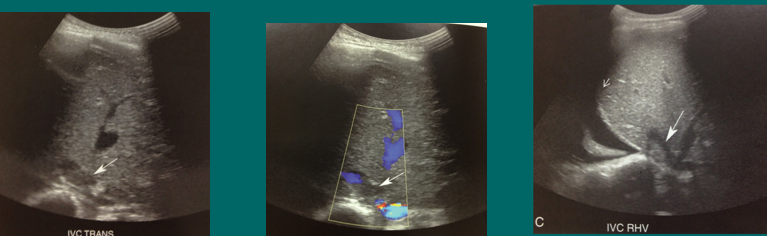

biliary complications

biloma (fluid collection)

PV gas